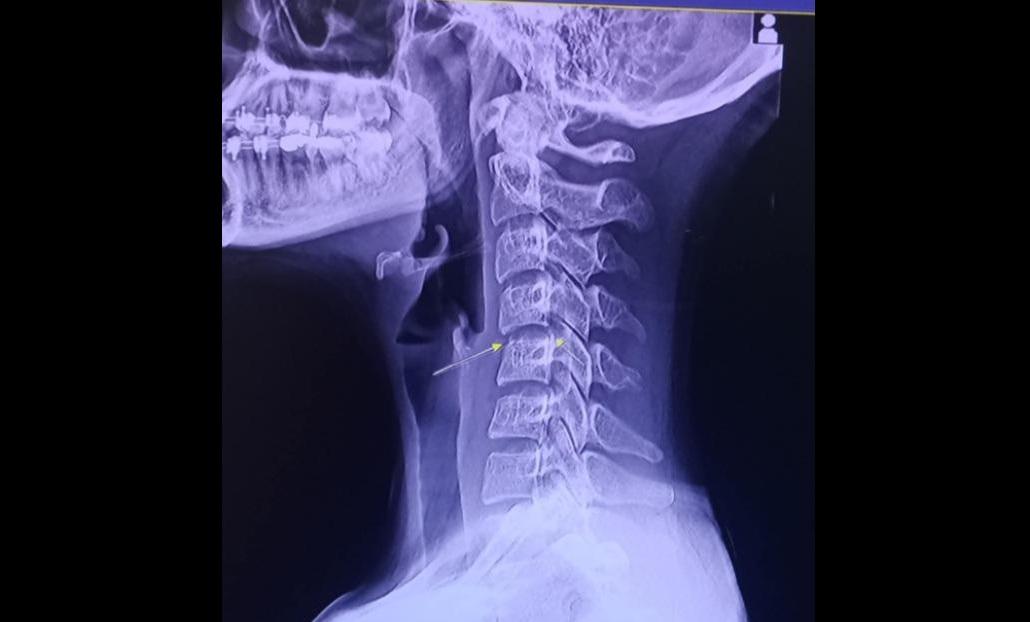

31歲的Phing Chayada因lock頸導致神經受損,最後死於與血管感染和腦部腫脹有關的併發症。(互聯網)

醫生診斷發現她的頸椎早已受傷,在按摩後導致神經受損,不幸演變成半身癱瘓,只能躺在床上。泰國傳媒指,Chayada最後死於與血管感染和腦部腫脹有關的併發症。